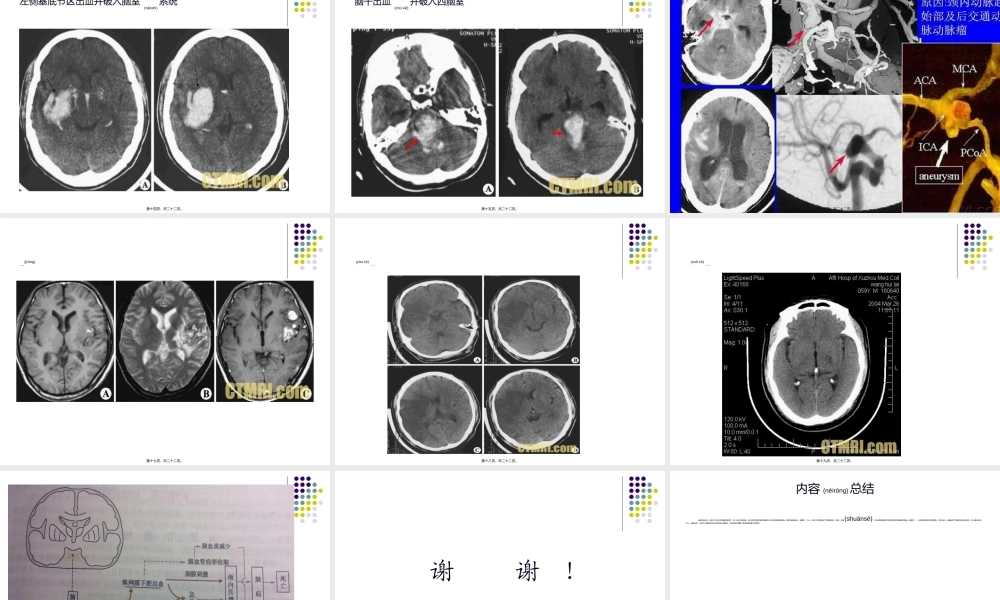

脑血管病分类(fēnlèi)王碧芬第一页,共二十二页。是一组由脑血管发生血液循环障碍(zhàngài)而引起的脑功能障碍(zhàngài)疾病。脑血管病CVD第二页,共二十二页。脑血管病的分类(fēnlèi)脑部静脉(jìngmài)血栓形成颅内静脉瘤、静脉窦及其他动脉性疾病脑动脉炎颅内血管畸形颅内动脉瘤高血压性脑病脑血管性痴呆椎-基底动脉供血不足脑卒中短暂性脑缺血发作发作第三页,共二十二页。短暂性脑缺血发作(fāzuò)颈动脉系统椎-基底动脉系第四页,共二十二页。脑卒中脑卒中又称中风或脑血管意外(yìwài),是一组以急性起病、局灶性或弥漫性脑功能缺失为共同特征的脑血管病,通常包括脑出血,脑梗死,SAH。脑卒中主要是由于血管壁异常,血栓,栓塞以及血管破裂等所造成的神经功能障碍性疾病。第五页,共二十二页。脑卒中SAH1、动脉瘤破裂引起:1)先天性动脉瘤2)动脉硬化性动脉瘤3)感染性动脉瘤2、血管畸形3、颅内异常血管网症4、其他脑出血1、高血压性脑出血2、继发于梗死的出血3、肿瘤性出血4、血液病引起5、淀粉样脑卒中6、动脉炎引起7、药物(yàowù)引起8、脑血管畸形或动脉瘤引起9、其他脑梗死1、动脉粥样硬化性血栓梗死2、脑栓塞:1)心源性2)动脉源性3)其他3、腔隙性梗死4、出血性梗死5、无症状性梗死6、其他第六页,共二十二页。脑出血脑出血是指原发于脑内动脉、静脉和毛细血管的病变出血,以动脉出血为多见,血液在脑实质内积聚形成脑内血肿。小量出血是血液仅渗透在神经纤维之间,对脑组织破坏较少;出血量较大时血液在脑组织内积聚形成血肿,血肿的占位效应(xiàoyìng)压迫周围脑组织、撕裂神经纤维间的横静脉是血肿进一步增大,血液成分特别是凝血酶、细胞因子血红蛋白的溶出等,致使血肿周围脑组织可在数小时内形成明显的脑水肿、缺血和点状微出血,血肿进一步扩大导致临近组织受压、移位以致形成脑疝。第七页,共二十二页。脑出血的分类(fēnlèi)壳核出血:大脑基底节为最常见的出血部位,约占脑出血的60%。脑桥出血:常突发起病,起病初可有意识,数分钟内进入昏迷,以交叉性瘫痪、凝视瘫肢、针尖样瞳孔为特征性症状。小脑出血:可发生(fāshēng)枕大孔疝。常诉一侧后枕部剧烈头痛和眩晕,呕吐频繁,发音含糊,病变侧肢体动作共济失调,但瘫痪不明显。脑室出血:多由于大脑基底节处出血后破入侧脑室,以致血液充满整个脑室和蛛网膜下腔系统。小脑出血和脑桥出血也可破入四脑...

2、本站所有内容均由合作方或网友上传,本站不对文档的完整性、权威性及其观点立场正确性做任何保证或承诺!文档内容仅供研究参考,付费前请自行鉴别。